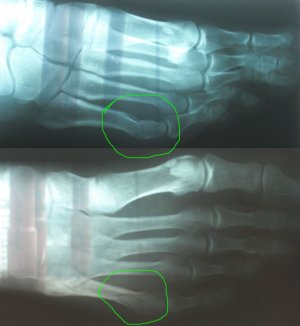

Снимок в реале не намного лучше, интересует место отмеченное кругом. Нога правая, верхнее фото - проекция с наружной стороны, нижнее фото - проекция сверху. Диагноз был поставлен перелом 5й плюсневой кости (без подробностей), впринципе по снимку это видно. поэтому и написал в этой теме. Подскажите тогда по выбору иммобилизации (и нужна ли она вообще) и ее срокам при таком повреждении.По такому плохому фото диагноз не ставят даже по снимку. Диагноз ставит врач при личном обращении пациента.

В данном случае какую иммобилизацию Вы бы рекомендовали и на какой срок? Работа связана с вождением автомобиля, т.е. давление на педали (нога правая). Когда можно приступать? После перелома полдня ездил нормально, до травмпункта доехал сам.Что то похожее на спиралевидный дистальный перелом.

35 лет. Рост 185. Вес 75. Как любитель занимаюсь активными видами спорта (виндсерфинг, сноуборд итд.). Перелом 17 марта от падения тяжелого предмета на стопу. Снимок сделан примерно через 3 часа.Я ведь про вас ничего не знаю, сколько лет,Ю ваша физическая форма, конституционный тип, время перелома...